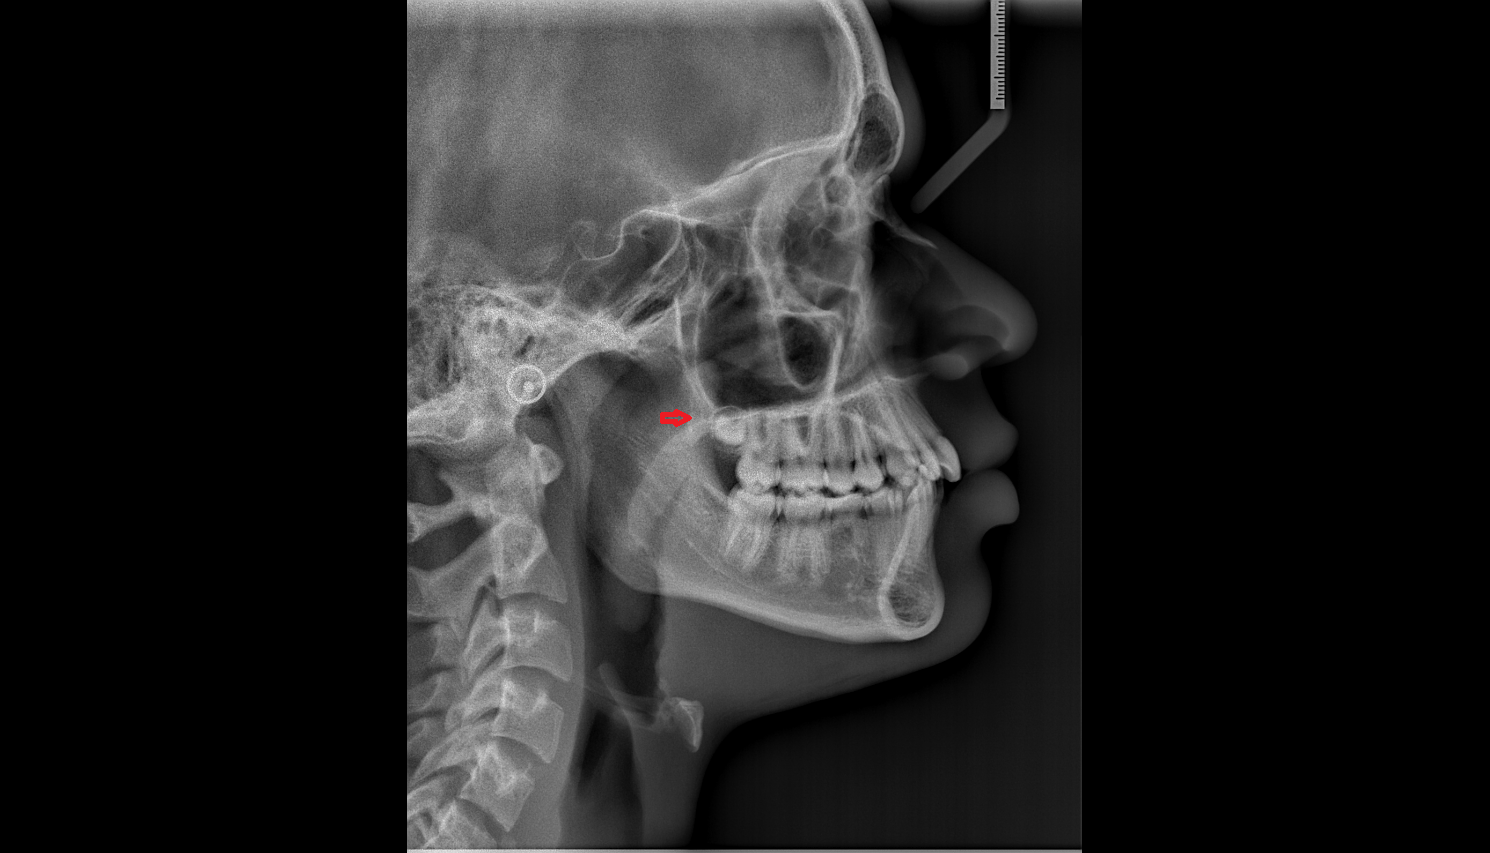

- Temporomandibular joint

- Mandibular condyle

- Mandibular fossa

- Ramus of mandible

- Neck of mandible

- Hyoid bone

- Body of hyoid bone

- Greater horn of hyoid bone